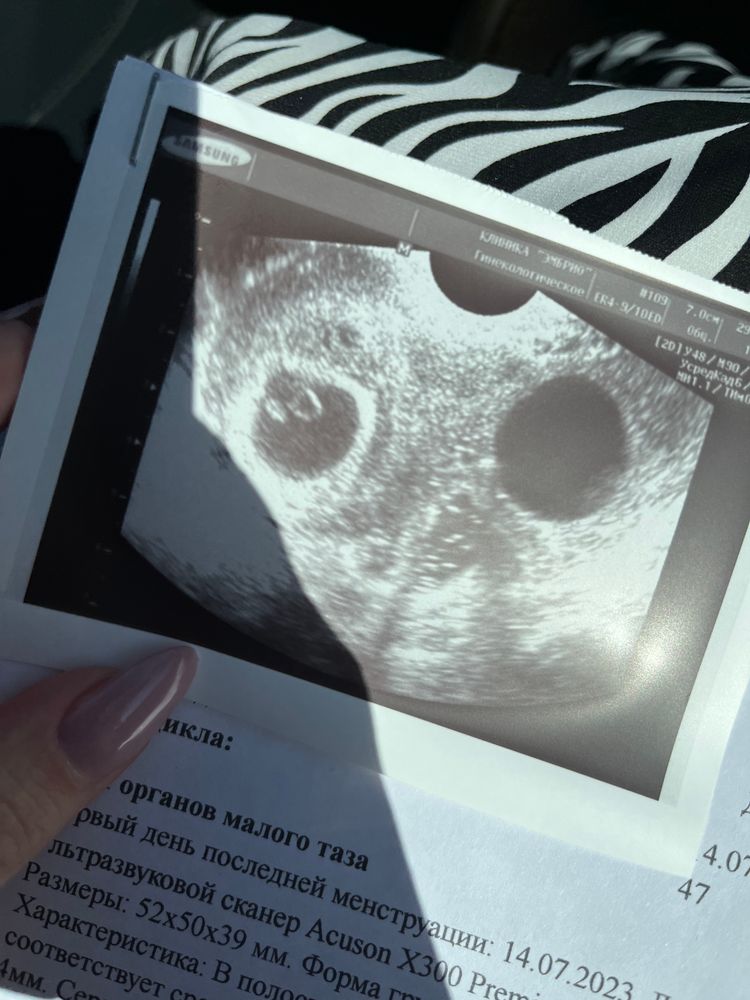

2 плодных яйца

Девочки, кто знает? Двойня на узи ранний срок